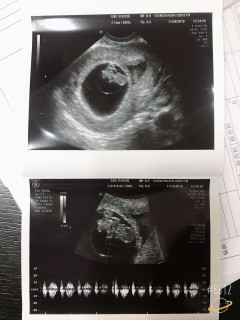

エコー確認中に赤ちゃん動いてる気がしました!大きさは順調で、19.2mmでした!出血もなく、なんの心配もかけず、産まれる前からいい子です(*^^*)次回の検診で不妊病院を卒業できます♪

妊娠が分かってから2回目の病院。初めての妊娠ということもあって検索魔になり、病院で診てもらう前の時期はいつも不安やじれったい気持ちで、ちゃんと16.2mmまで大きくなって心音も聞かせてもらって一安心でした。また2週間後ですがエコーはずっと見ていても飽きないぐらい早く次に見れる日が待ち遠しい。